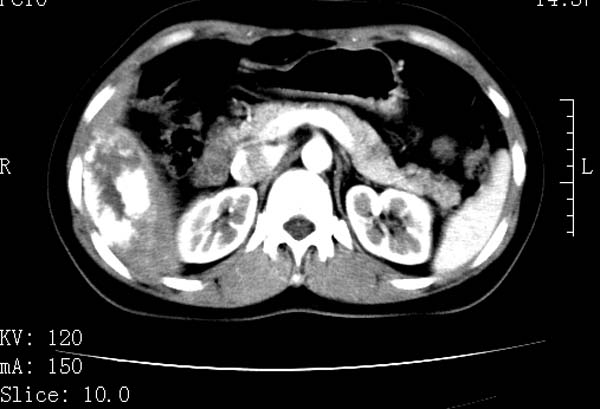

标题: CT22086:女44岁 肝右叶占位增强示巨大血管瘤,门脉期发现小 [打印本页]

标题: CT22086:女44岁 肝右叶占位增强示巨大血管瘤,门脉期发现小

请大家观察一下小灶   发表意见,谢谢

支持肝右叶血管瘤诊断。 小病灶亦考虑血管瘤改变。温习一下:

肝海绵状血管瘤ct平扫常呈均匀低密度,与邻近血管密度相仿。在脂肪肝背景下可呈相对高密度。在增强扫描时,一般早期(动脉期)呈周边结节状或弧形强化,其密度与同层面的血管密度相仿,随着时间延迟向中央渐进性充填,注药后5~7分钟,逐渐扩大至全瘤强化,强化密度逐渐降至稍高于或等于正常肝脏。大的血管瘤往往中央有星形、大的低密度区,可以为纤维化或囊性变所致,纤维化成分可在延迟2 o分钟时完全充填,呈等密度,但囊变区则不会强化。不典型ct表现常见于≤3 cm的小血管瘤。小的血管瘤可以在动脉期即呈全部致密的均匀强化,不呈典型的周边结节状强化表现,但其密度往往较高,与主动脉相仿,在延迟期呈高或等密度。其他不典型的ct表现有:增强扫描强化不明显,呈点状较轻程度的强化,充填慢,可能与供血动脉较细和较大的血管间隙有关以及中央先强化等。

延迟扫描三个病灶都呈等密度改变。肝多发血管瘤,较典型。